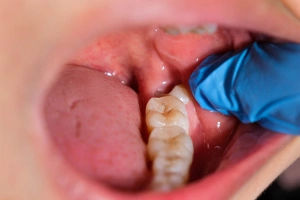

Food trapping behind the last molar

Partially erupted tooth causing cheek biting

Gum gently opened to access tooth

Sectioning (if needed)

Tooth removed while protecting nerves